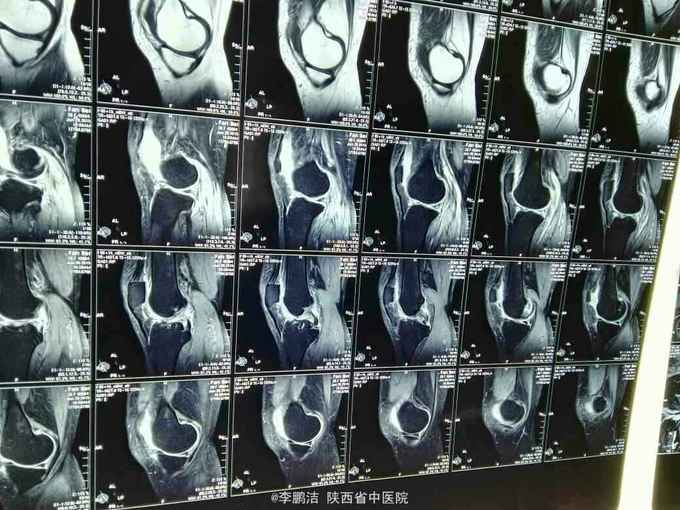

主诉:双膝关节疼痛,间断发作4年余。 现病史:患者于入院4年前因劳累后出现双膝关节疼痛,久行及上下楼梯时疼痛加剧,经休息疼痛好转,故当时未能引起重视,未进行系统治疗。其后因疼痛在当地诊所行局部理疗(具体治疗不详),经治疗后疼痛当时好转。之后,双膝关节疼痛症状时轻时重,间断性发作。近来,双膝关节疼痛症状加重,患者为求进一步治疗,遂于今日来我院就诊,门诊以“膝骨关节病”之诊断收住我科。

查体:脊柱生理弯曲尚可,L3-S1棘突及椎旁无压痛,双膝关节无肿胀,局部皮肤温度不高,内外侧副韧带止点压痛(+),髌韧带止点处压痛(-),鹅足滑囊处压痛(+),浮髌试验(-),髌骨摩擦试验(+),抽屉试验(-),双膝关节活动度明显受限;生理反射存在,病理反射未引出。

中医诊断:骨痹症 气滞血瘀 西医诊断:1、膝骨关节病 2、2型糖尿病 3、高血压 中医治疗方案:中药封包治疗、穴位贴敷舒筋通络。 西医治疗方案:口服阿托伐他汀钙片降脂,盐酸二甲双胍片、阿卡波糖片降糖,苯磺酸左旋氨氯地平片降压,硫酸氨基葡萄糖胶囊保护软骨面;患者夜间出现胸闷、气短,可行动态心电图、活动平板试验排除心脏疾病。 可给予口服活血化瘀,行气宽中之中药汤剂,具体方剂如下: 生地黄25g 当归10g 川芎15g 桃仁10g 红花10g 赤芍15g 柴胡10g 枳壳10g 怀牛膝15g 桔梗10g 生甘草6g 黄连10g 半夏(清半夏)15g 瓜萎15g 山栀10 7付水煎服 一日一剂